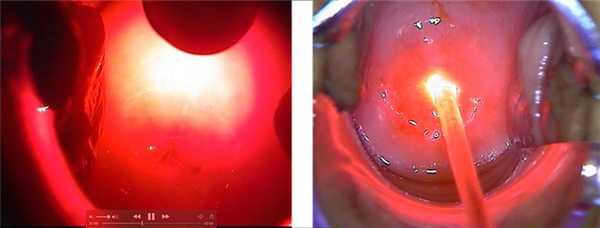

В статье представлен собственный опыт десятилетнего клинического наблюдения пациентки с меланобластомой хориоидеи глаза после проведения органосохраняющего лечения с использованием комбинированного метода лечения, включающего транспупиллярную термотерапию и фотодинамическую терапию. Через десять лет наблюдения пациентка жива без признаков прогрессирования и рецидива заболевания. Таким образом ранняя диагностика злокачественных новообразований глаза позволяет применять современное высокотехнологичное органосохраняющее лечение и позволяет сохранить зрительную функцию глаза и оптимально решить вопросы социальной, бытовой и трудовой реабилитации. Выбор органосохраняющего метода лечения больных с меланобластомой хориоидеи глаза необходимо всегда решать совместно с онкологом и офтальмологом, выполнять его только в специализированном медицинском учреждении и обеспечивать строгое динамическое наблюдением за больным.

При проведении фотодинамической терапии вводился внутривенно болюсно фотосенсибилизирующий препарат Радахлорин 3 мг/кг и проводилось облучение лазерным излучением с использованием лазерного фотодинамического комплекса Лидия, построенного на базе лазерного аппарата АЛХТ-ЭПОМЕД с длиной волны 662 нм. Транспупиллярное воздействие осуществляли лазерным излучением с длиной волны 810 нм с экспозицией времени 60 сек в каждой точке воздействия с нанесением аппликаций в виде черепицы до полного равномерного побеления опухоли. Воздействие осуществляли с мощностью 200-1 700 мВт в два этапа. На первом этапе в зависимости от размера опухоли, ее конфигурации и близости к сенсорным отделам сетчатки, использовали диаметр фокального пятна размером 1,0 или 1,8 или 3,0 или 5,0 мм. На втором этапе, через четверо суток, использовали диаметр фокального пятна размером 0,6 или 0,8 мм. При этом облучали только те участки, которые восстановили исходный цвет, существовавший до первого этапа воздействия.

Пациентка О. с 13.09.2006 г. по 02.10.2006 г. прошла курс комбинированного лечения путем проведения фотодинамической терапии с фотосенсибилизатором Радахлорин. 26.09.2006 года пациентке проведена транспупиллярная термотерапия новообразования.

При выписке из клиники: офтальмоскопически появились четкие границы образования, частичное рассасывание образования, в центре которого кратер на месте регрессии опухоли, визуально размер около 4 мм. Острота зрения правого глаза 1,0, левого глаза 0,1, sph +2,0D = 0,7.

Пациентка О. находится на диспансерном наблюдении на протяжении десяти лет без признаков рецидива заболевания. В настоящее время острота зрения правого глаза 0,4, sph +2,0D = 1,0, левого глаза 0,5 sph +2,5D = 0,5. При офтальмоскопии правого глаза: положение глаза в орбите правильное, движения в полном объеме. Коньюктива бледно-розовая. Роговица прозрачная, гладкая. Передняя глазная камера средней глубины, влага прозрачная. Радужка структурирована, пигментная кайма сохранена. Глазное дно: диск зрительного нерва бледно-розовый, границы четкие, сосудистый пучок в центре, экскавация 0,4. При офтальмоскопии левого глаза: диск зрительного нерва бледно-розовый, четко оконтурирован, в нижнем наружном квадранте обширный рубец хориоидеи, хориосклероз.

Возможность применения органосохраняющего комбинированного метода лечения больных меланобластомой хориоидеи глаза с использованием транспупиллярной и фотодинамической терапии позволяет сохранить зрительную функцию глаза и оптимально решить вопросы социальной и трудовой реабилитации.